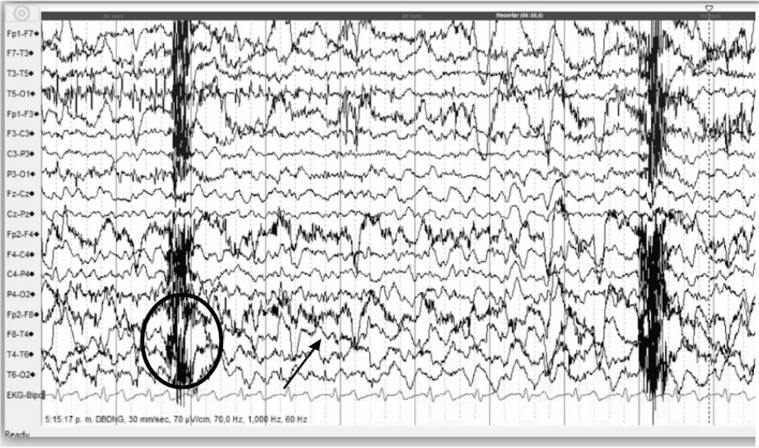

内侧颞叶硬化(MTS)突出作为一个普遍的病因医学难治性颞叶癫痫。了解MTS的病理改变、临床表现和危险因素对认识和怀疑MTS至关重要。在本文中,我们对MTS的病理生理、临床表现和治疗方案进行了全面的综述,目的是提供对这种疾病的最新了解。

Mesial temporal sclerosis (MTS) stands out as a prevalent etiology of medically intractable temporal lobe epilepsy. Understanding the pathological alterations, clinical manifestations and risk factors of MTS is crucial for the recognition and suspicion of this condition. In this paper, we provide a comprehensive narrative review on the pathophysiology, clinical manifestations, and treatment options for MTS. By doing so, we aim to provide an up-to-date understanding of this condition.